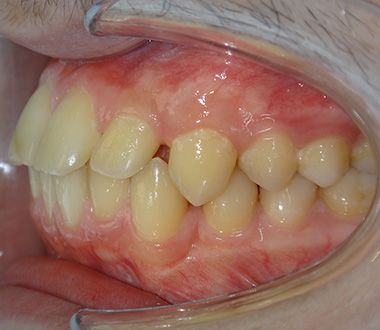

Glenn T. broke 2 teeth as a result of an accident in his childhood. These teeth were filled and the fillings were aged. Glenn was unhappy because of the gaps between his teeth. He also did not like the angle of his front two teeth. He wanted to have his teeth done before he started university. He decided to have invisalign in Turkey with his family.

Firstly, we treated the gap between the teeth with Invisalign. We also corrected the angle of the front teeth. Invisalign Lite was enough. Glenn visited Turkey 4 times in a period of 8 months. During his last visit, we replaced the old fillings in his front teeth with composite bonding. We performed lingual retrainer to maintain the alignment of the teeth. We produced an sx plate for him to use at night and delivered it to him. Glenn was very happy. He said he wanted to study at a dentistry faculty.